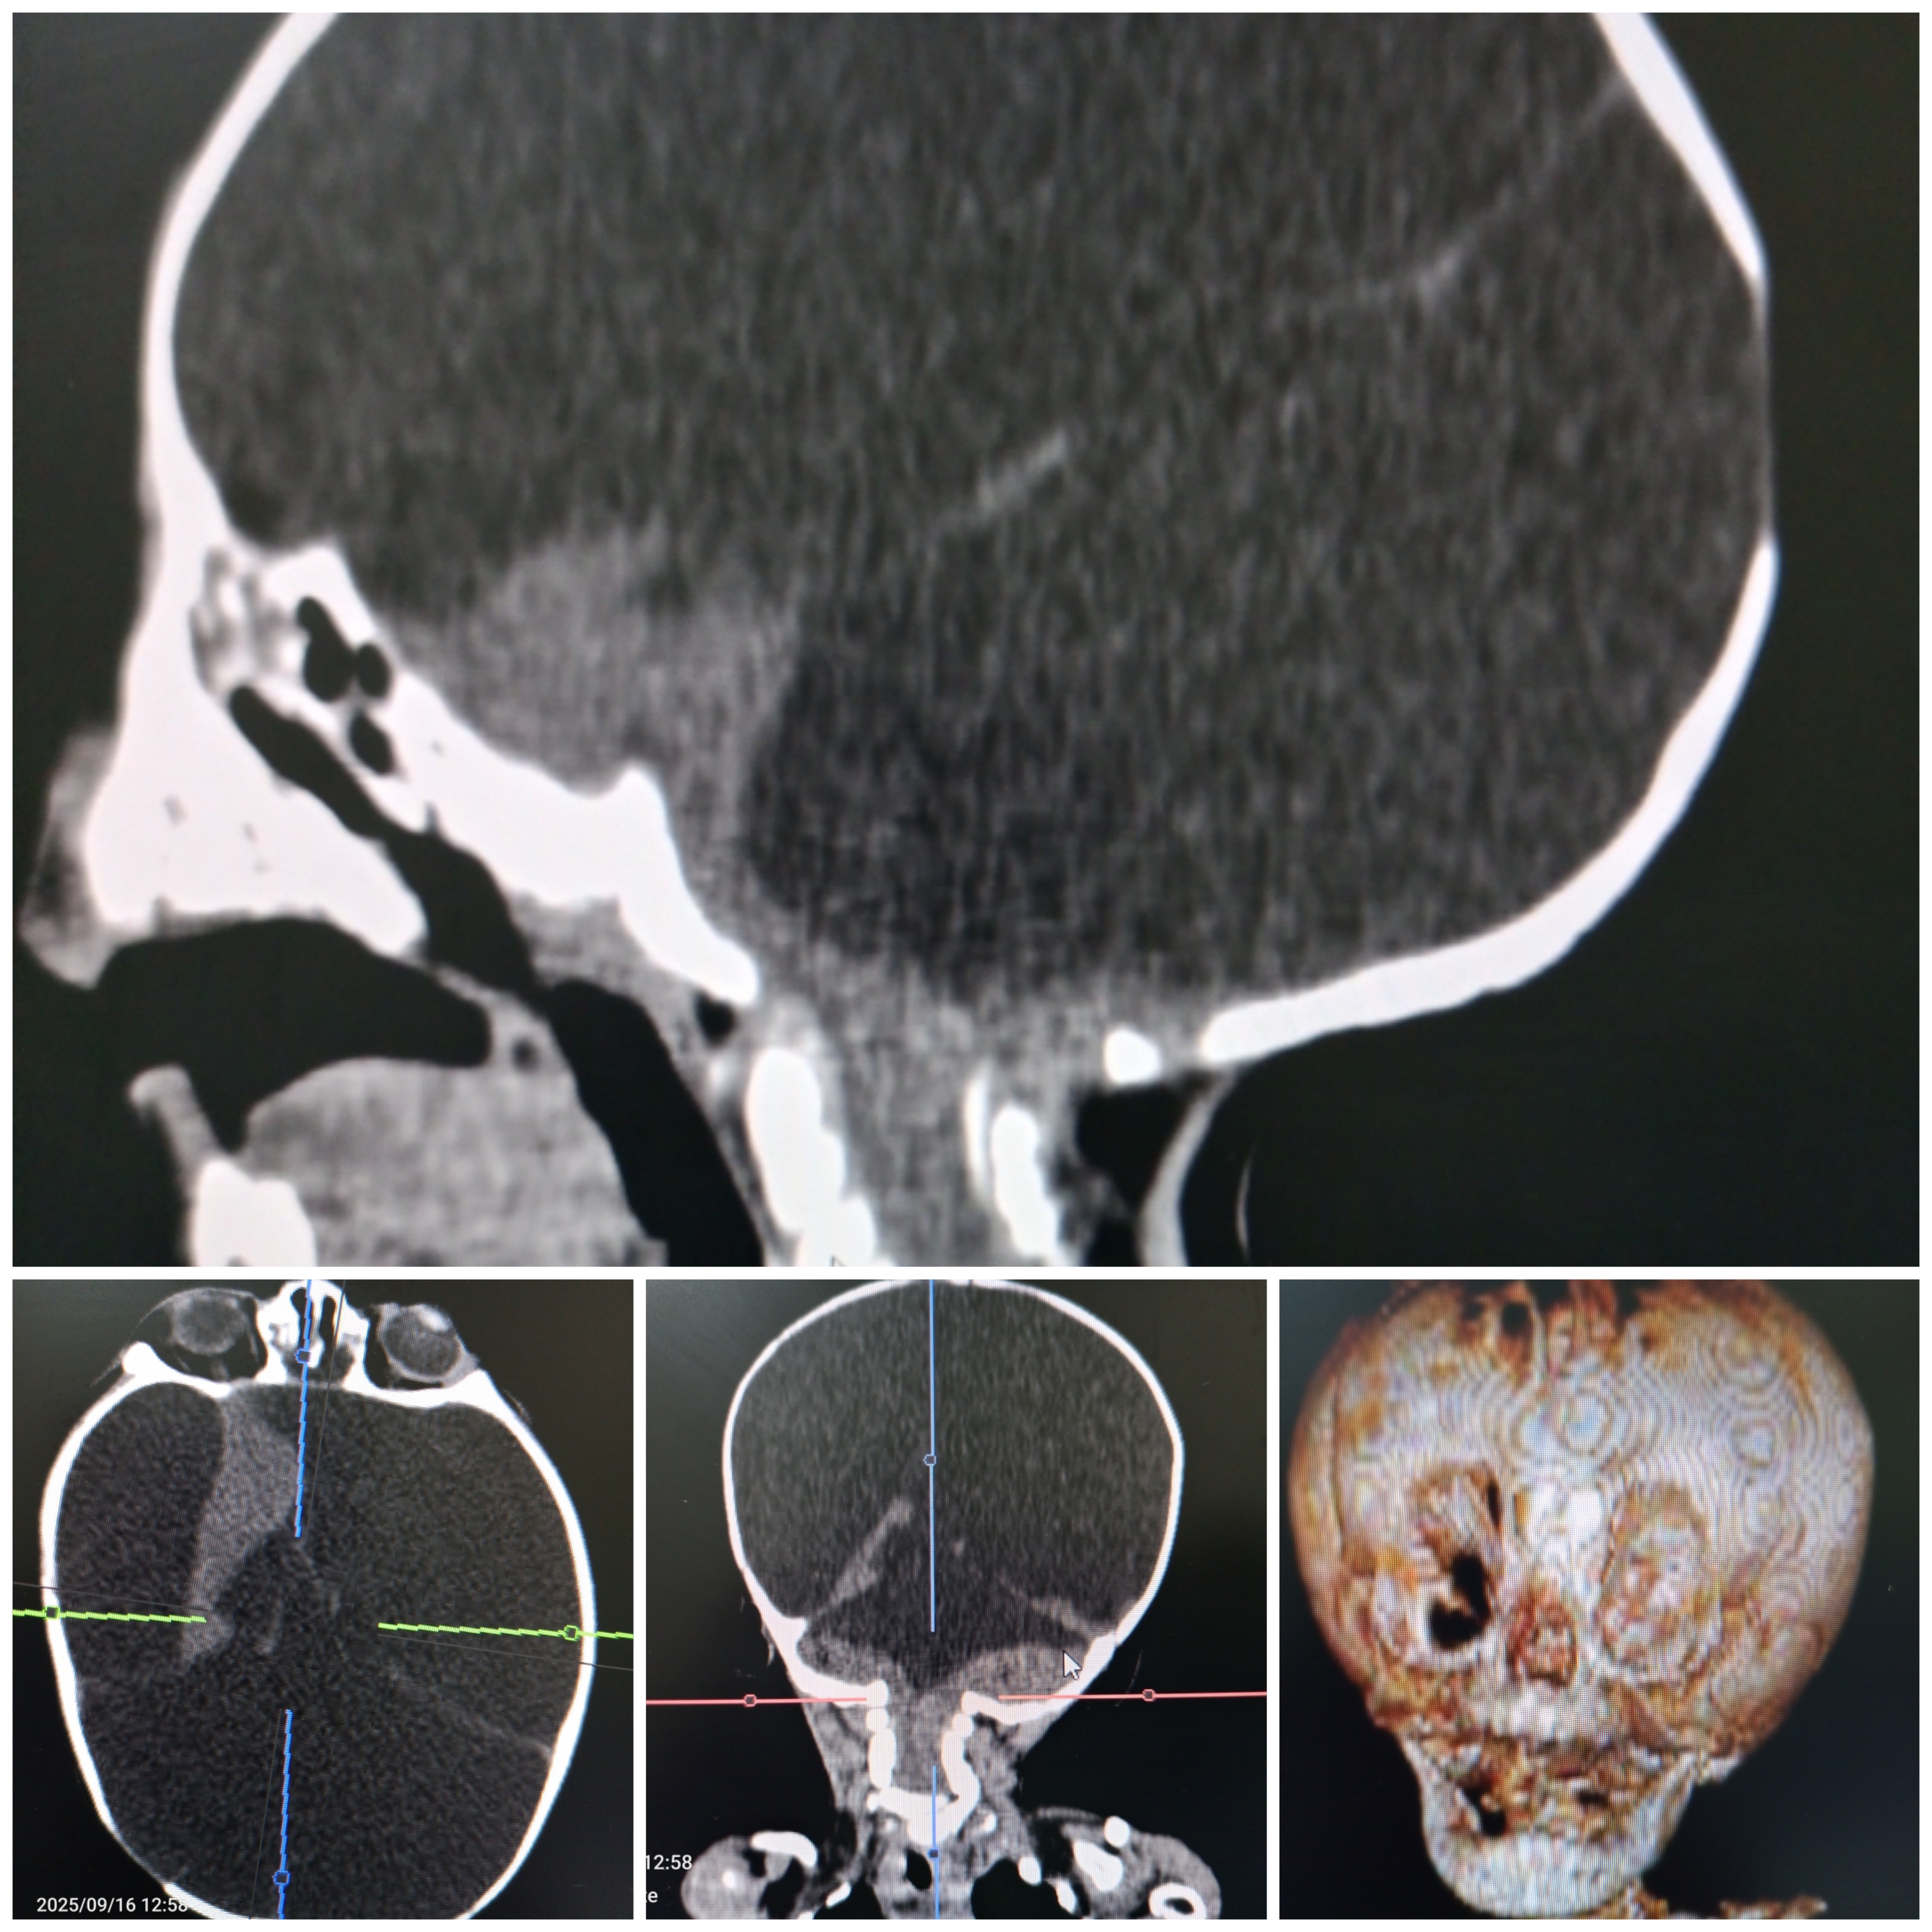

Macrocrâne de nourrisson agé de 7mois

Publié par : Kamal nadifi